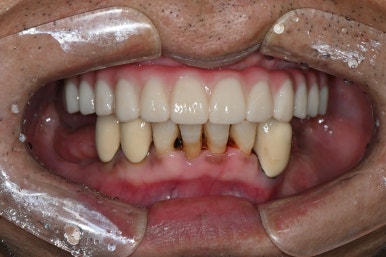

강남 풀아치 임플란트 (좌: 2024년 7월 1일, 우:2024년 9월 23일 완성)

디지털 풀아치 임플란트가 완성된 모습

최종 완성된 디지털 풀아치 임플란트 (상악)